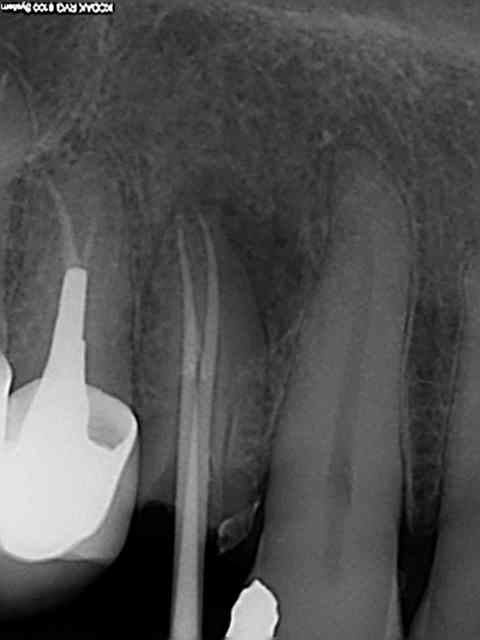

Bon je n'avais pas mis la digue sur cette 14 en 2009. A votre avis la peche en 2014 est elle due à ca ? Moralité toujours mettre de l'angulation dans les radios.